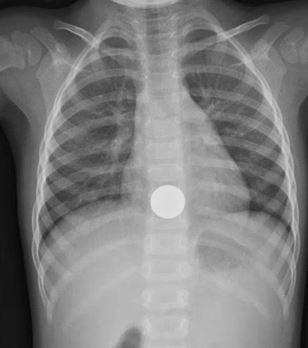

What’s the Diagnosis? @emdaily.cooperhealth.org